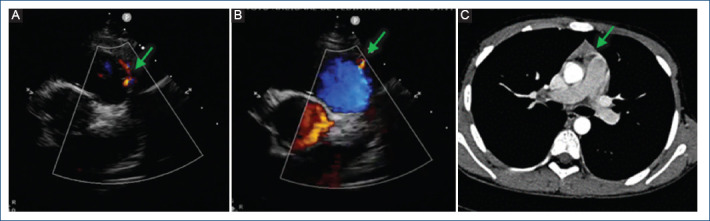

[Double coronary fistula: a rare finding in a pediatric patient].